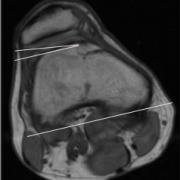

In this patient, the angle is less than 11 degrees, and thus the wall of the trochlea is considered to be dysplastic, or flatter than normal.

The LTI is an MRI calculation of the angle between the lateral edge of the femoral notch and the posterior edge of the femur at the level of the femoral epicondyles.

To measure the angle, one draws the line along of the wall of the trochlear groove underneath the cartilage layer. Then a line is drawn at the back of the two condyles - from it a parallel line can be extrapolated to meet the first one, to make it easier to see the angle.

If the LTI is 20-22 degrees the slope of the wall of the trochlea is considered normal. However, if it is below 11 degrees it is considered dysplastic. For some severely affected people it can be even zero or less. A flattened dysplastic trochlea makes it easier for a patella to sublux or to dislocate, and thus this angle is important to calculate when assessing the causes of such patellar instability.